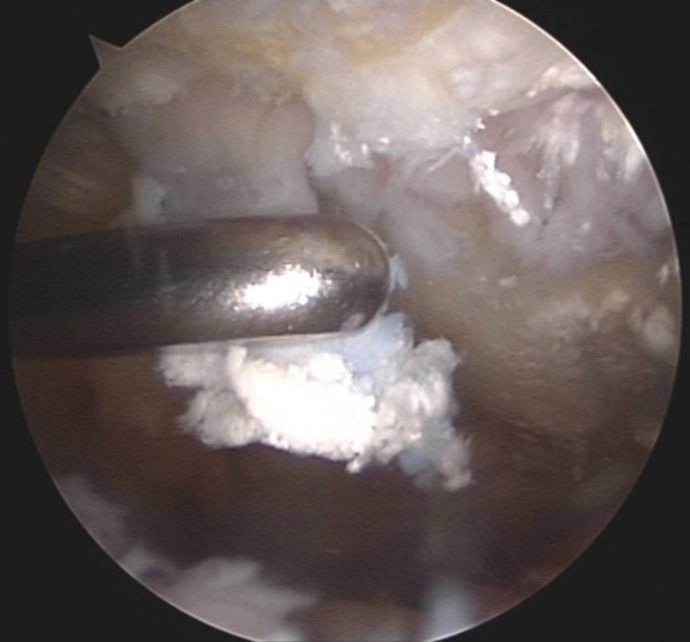

关节镜下的结晶

手术治疗则是针对,直径>1.5 cm的痛风石,及引发骨关节炎的结晶沉淀,进行清除。如果是单纯的取痛风石,多数可以通过关节镜微创手术完成,创口较小,避免大范围的开放性伤口。